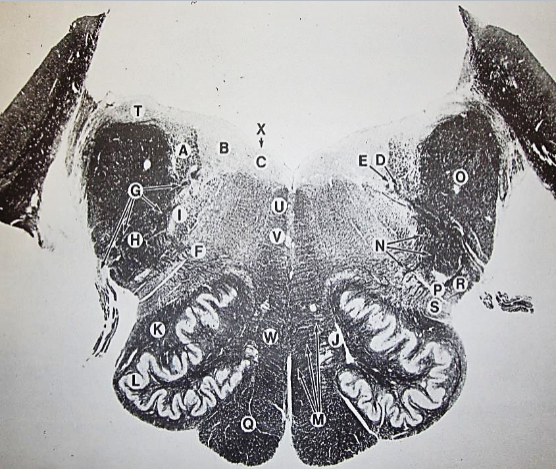

A

Fasciculus gracilis

B

gracile nucleus

C

fasciculus cuneatus

D

cuneate nucleus

E

spinal trigeminal tract

F+G collectively

spinal trigeminal nucleus

H

accessory nucleus

I

pyramidal decussation

J

rubrospinal tract

K

posterior spinocerebellar tract

L

anterior spinocerebellar tract

M

lateral spinothalamic tract

N

anterior spinothalamic tract

O

lateral vestibulospinal tract

P

medial longitudinal fasciculus

Q

tectospinal tract

A

Lateral Cuneate nucleus

B

dorsal external arcuate fibers

C + D collectively

vestibular nuclei

C + D collectively

vestibular nuclei

E

dorsal motor nucleus of vagus nerve

F

solitary fasciculus

G

solitary nucleus

H

nucleus ambiguous

I

fascicles of glossopharyngeal nerve

J

hypoglossal nucleus

K

fascicles of hypoglossal nerve

L

dorsal longitudinal fasciculus

M

central tegmental tract

N

inferior olivary nucleus

R

inferior cerebellar peduncle

S

spinal trigeminal tract

T

spinal trigeminal nucleus

U

ventral trigeminothalamic tract

V

pyramidal (corticospinal) tract

W

rubrospinal tract

X

anterior spinocerebellar tract

Y

spinal lemniscus

Z

medial longitudinal fasciculus

a

tectospinal tract

b

medial lemniscus

c

vagus nerve

d

inferior salivatory nucleus